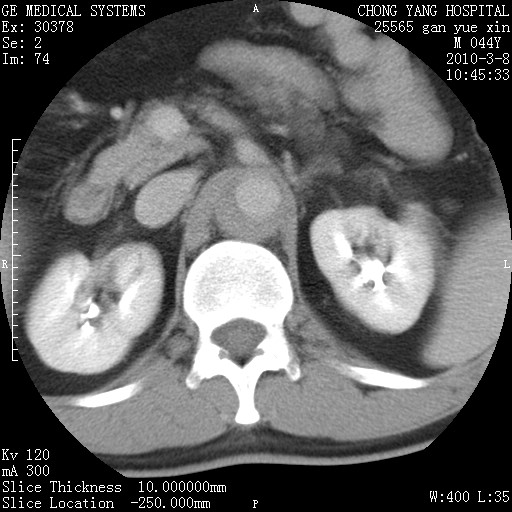

标题: CT24940:主动脉增强,典型病例。 [打印本页]

标题: CT24940:主动脉增强,典型病例。

夹层动脉瘤。

动脉夹层

夹层动脉瘤,典型

主动脉夹层。

动脉夹层的分型:

⒈debakey分型:根据主动脉夹层累及部位,分为三型:ⅰ型:原发破口位于升主动脉或主动脉弓部,夹层累及升主动脉、主动脉弓部、胸主动脉、腹主动脉大部或全部,少数可累及髂动脉。ⅱ型:原发破口位于升主动脉,夹层累及升主动脉,少数可累及部分主动脉弓。ⅲ型:原发破口位于左锁骨下动脉开口远端,根据夹层累及范围又分为ⅲa,ⅲb。ⅲa型:夹层累及胸主动脉。ⅲb型:夹层累及升主动脉、腹主动脉大部或全部。少数可累及髂动脉。

⒉stanford分型:a型:夹层累及升主动脉,无论远端范围如何。b型:夹层累及左锁骨下动脉开口以远的降主动脉。

夹层动脉瘤,少量胸水

夹层动脉瘤;左侧少量胸腔积液。

典型主动脉夹层。